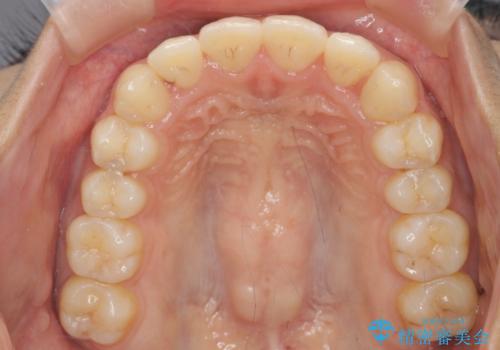

前歯のねじれ、すれ違いを改善 部分ワイヤー+マウスピース矯正

- 上下前歯のすれ違い、ねじれのある歯並びの矯正治療を求めて来院されました。

上顎前歯のみの部分ワイヤー治療を約6ヶ月行い、ねじれの問題を解決したのち、マウスピース矯正で細かな歯列を整えていきます。

前歯のすれ違いが改善することで噛みやすくなった。と矯正治療の結果に満足いただくことができました。